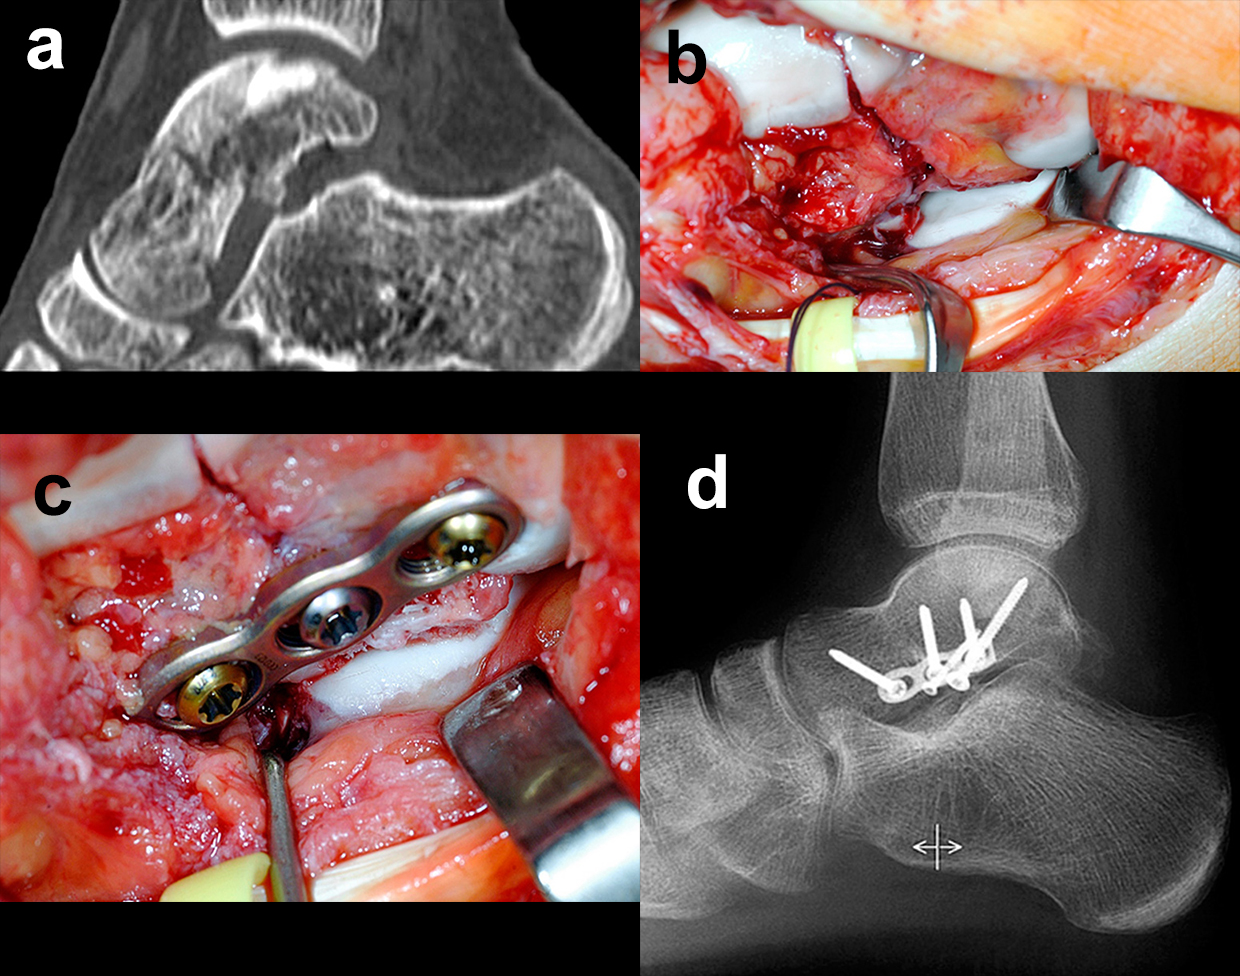

Die Zugänge zu dislozierten Taluskorpusfrakturen entsprechen im Wesentlichen denen bei Talushalsfraktur. Bei weit in den zentralen und hinteren Taluskorpus hineinreichenden Frakturen kann zur ausreichenden Übersicht und verbesserten Fragmentmanipulation eine Innenknöchelosteotomie erforderlich werden, sofern der Innenknöchel nicht ohnehin mit frakturiert ist 4. Hierzu wird der anteromediale Zugang nach proximal erweitert. Die Schraubenkanäle werden vorgeborht um eine exakte Refixierung des Innenknöchels nach der Talusosteosynthese zu gewährleisten. Die Osteotomie wird schräg auf den medialen Gelenkwinkel geführt, im eigenen Vorgehen zur besseren Stabilisierung vorzugsweise als Chevron-Osteotomie. Das Subtalargelenk ist bei Taluskorpusfrakturen regelhaft frakturiert und disloziert (Abb. 11). Zur Reposition und Überprüfung der Gelenkkongruenz im Subtalargelenk wird ein zusätzlicher anterolateraler Zugang benötigt.

Die anatomische Reposition erfolgt schrittweise unter direkter visueller Kontrolle von medial und lateral. Die temporäre Retention wird wiederum mit Kirschnerdrähten erzielt (Abb. 12). Die Hauptfragmente werden durch Schrauben, die unter Knorpelniveau versenkt werden, fixiert. Bei sagittalen Taluskorpusfrakturen werden daher vorzugsweise Doppelgewindeschrauben verwendet 34. Zur Fixierung kleinerer osteochondraler Fragmente werden vorzugsweise resorbierbare Stifte verwendet (Abb. 13). Zur Stabilisierung ausgedehnter medialer oder lateraler Trümmerzonen können anatomisch angepasste winkelstabile Platten verwendet werden. Bei diesen ist darauf zu achten, dass diese weder das Talonavicular-Gelenk noch den Innenknöchel irritieren. Gleiches gilt auch für Taluskopffrakturen, welche jedoch eher im Rahmen von Chopart-Luxationsfrakturen entstehen 12.

Zur Vollansicht und zum Lesen der Bildbeschreibung bitte die Bilder anklicken.